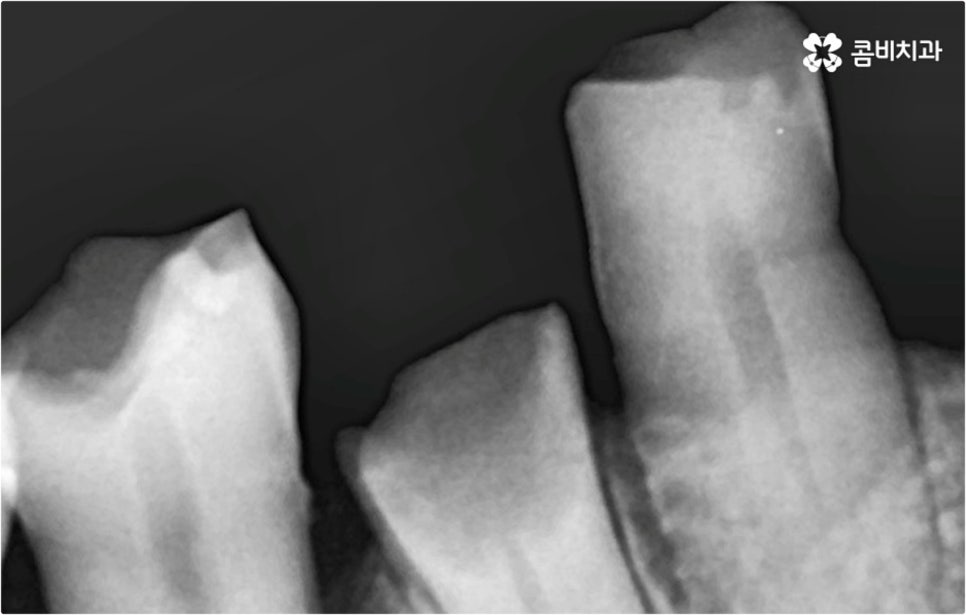

이때 환자분들의 상황에 따라서 임플란트 시술이 어려운 분들도 있을 수 있고 시술 전에 다른 치료를 선행해야 하는 분들도 있을 수 있기 때문에 먼저 꼼꼼하게 검진을 받아보실 필요가 있습니다. 특히 대다수의 치아를 잃어버리고 전악임플란트 를 진행하시는 분들의 경우 원인에 따라서 대처 방법이 다를 수 있는데요.

예를 들어 사고를 통해 한꺼번에 여러 개의 치아가 부러지거나 빠진 경우 연령 또는 전신 질환 여부 등을 살펴보고 치조골 상태가 양호하다면 보다 빠르고 간편한 당일 식립 방식을 이용해 볼 수 있어요. 그러나 하나 둘씩 치아가 빠질 때 마다 제때 치료를 해 주지 않아 치료 시기를 놓치고 결과적으로 무치악 상태에 이른지 오래 된 경우 또는 틀니를 오래 착용하여 잇몸뼈가 이미 많이 내려앉은 경우라면 바탕이 되는 잇몸뼈를 보충해 준 후 식립을 진행하는 방식을 이용해야 할 거예요.

또한 상악동과의 거리가 짧다면 거상술을 선행해야 할 수도 있고 심각한 치주 질환이 원인이라면 이를 먼저 깨끗하게 치료해 준 후 식립을 진행해야 성공률 또는 지속률이 높아질 수 있어요.